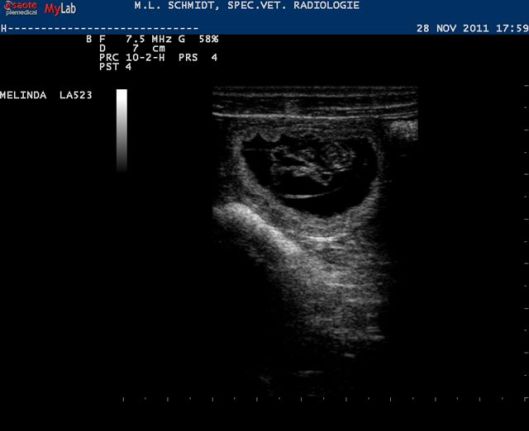

Vanavond hebben we de echo gedaan, en dit is de uitslag waar we op gehoopt hadden ;>

Op deze flipperkast was het vervolgens allemaal prima te zien. “Het zijn er veel” was de eerste opmerking van Chantal de dierenarts. “Tja, wat is veel?” was mijn wedervraag. De schatting bleef steken bij 6 tot 7; dat is eigenlijk precies de gemiddelde nestgrootte van een whippet. Uiteindelijk blijft het een verrassing; er kunnen nog vruchtjes afsterven in de komende tijd, maar er kunnen er vandaag ook nog wel ongezien zijn gebleven.

Ik vond wel, dat de kwaliteit van de echo iets minder was dan destijds met Jewel; het komt waarschijnlijk doordat er omhoog geduwd moet worden met de sensor. De automatische reactie van Hinde was om haar rug omhoog te trekken, die moesten we dus wat omlaag duwen, al met al denk ik dat het contact daardoor iets minder goed zal zijn geweest.

Maar goed, de frutseltjes waren toch wel goed te onderscheiden. De afmeting van de vruchtblaas waar ze inzitten werd ook nog gemeten: 3,3 centimer; de maat van een walnoot ongeveer.